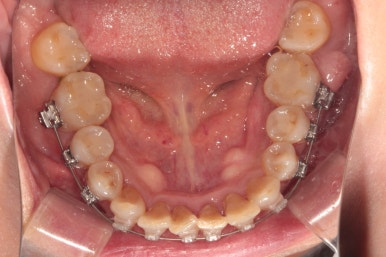

이제 정말 많이 배열이 완성되었습니다. 아래 앞니를 배열시키느라 시간이 조금 더 걸렸던 것 같아요.

씹는면에서 보아도 상당히 가지런히 완성된 것을 보실 수 있습니다.

교정치료가 끝나면 혀쪽에 유지장치를 붙여드리는데요, 치석이 보다 덜 생기도록 하기 위해서 치아 표면 그대로의 모양을 따라가는 와이어를 제작하여 부착해드리고 있습니다.

조금 더 비용을 들이더라도 정성담긴 모양의 유지장치입니다!!

치아 사이 공간까지도 완벽하게 밀착하고 지나가야 좋은 고정식 유지장치입니다. 그래야 치석도 덜 생기고 관리가 편해지시거든요..